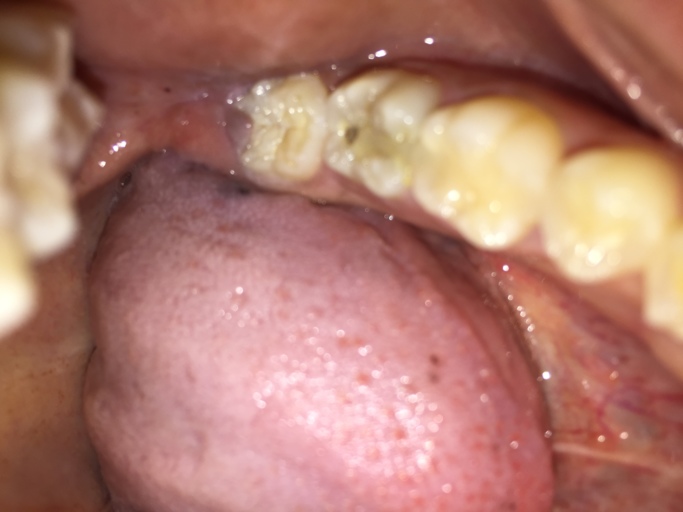

Is the hole in my tooth a cavity or broken composite filling?

Hello, I have a question about my back molar on the bottom row. I have had white composite fillings as well as sealants in the past years ago. It appears I have a hole in my tooth and it looks as though the filling has broken leaving a nice sized...